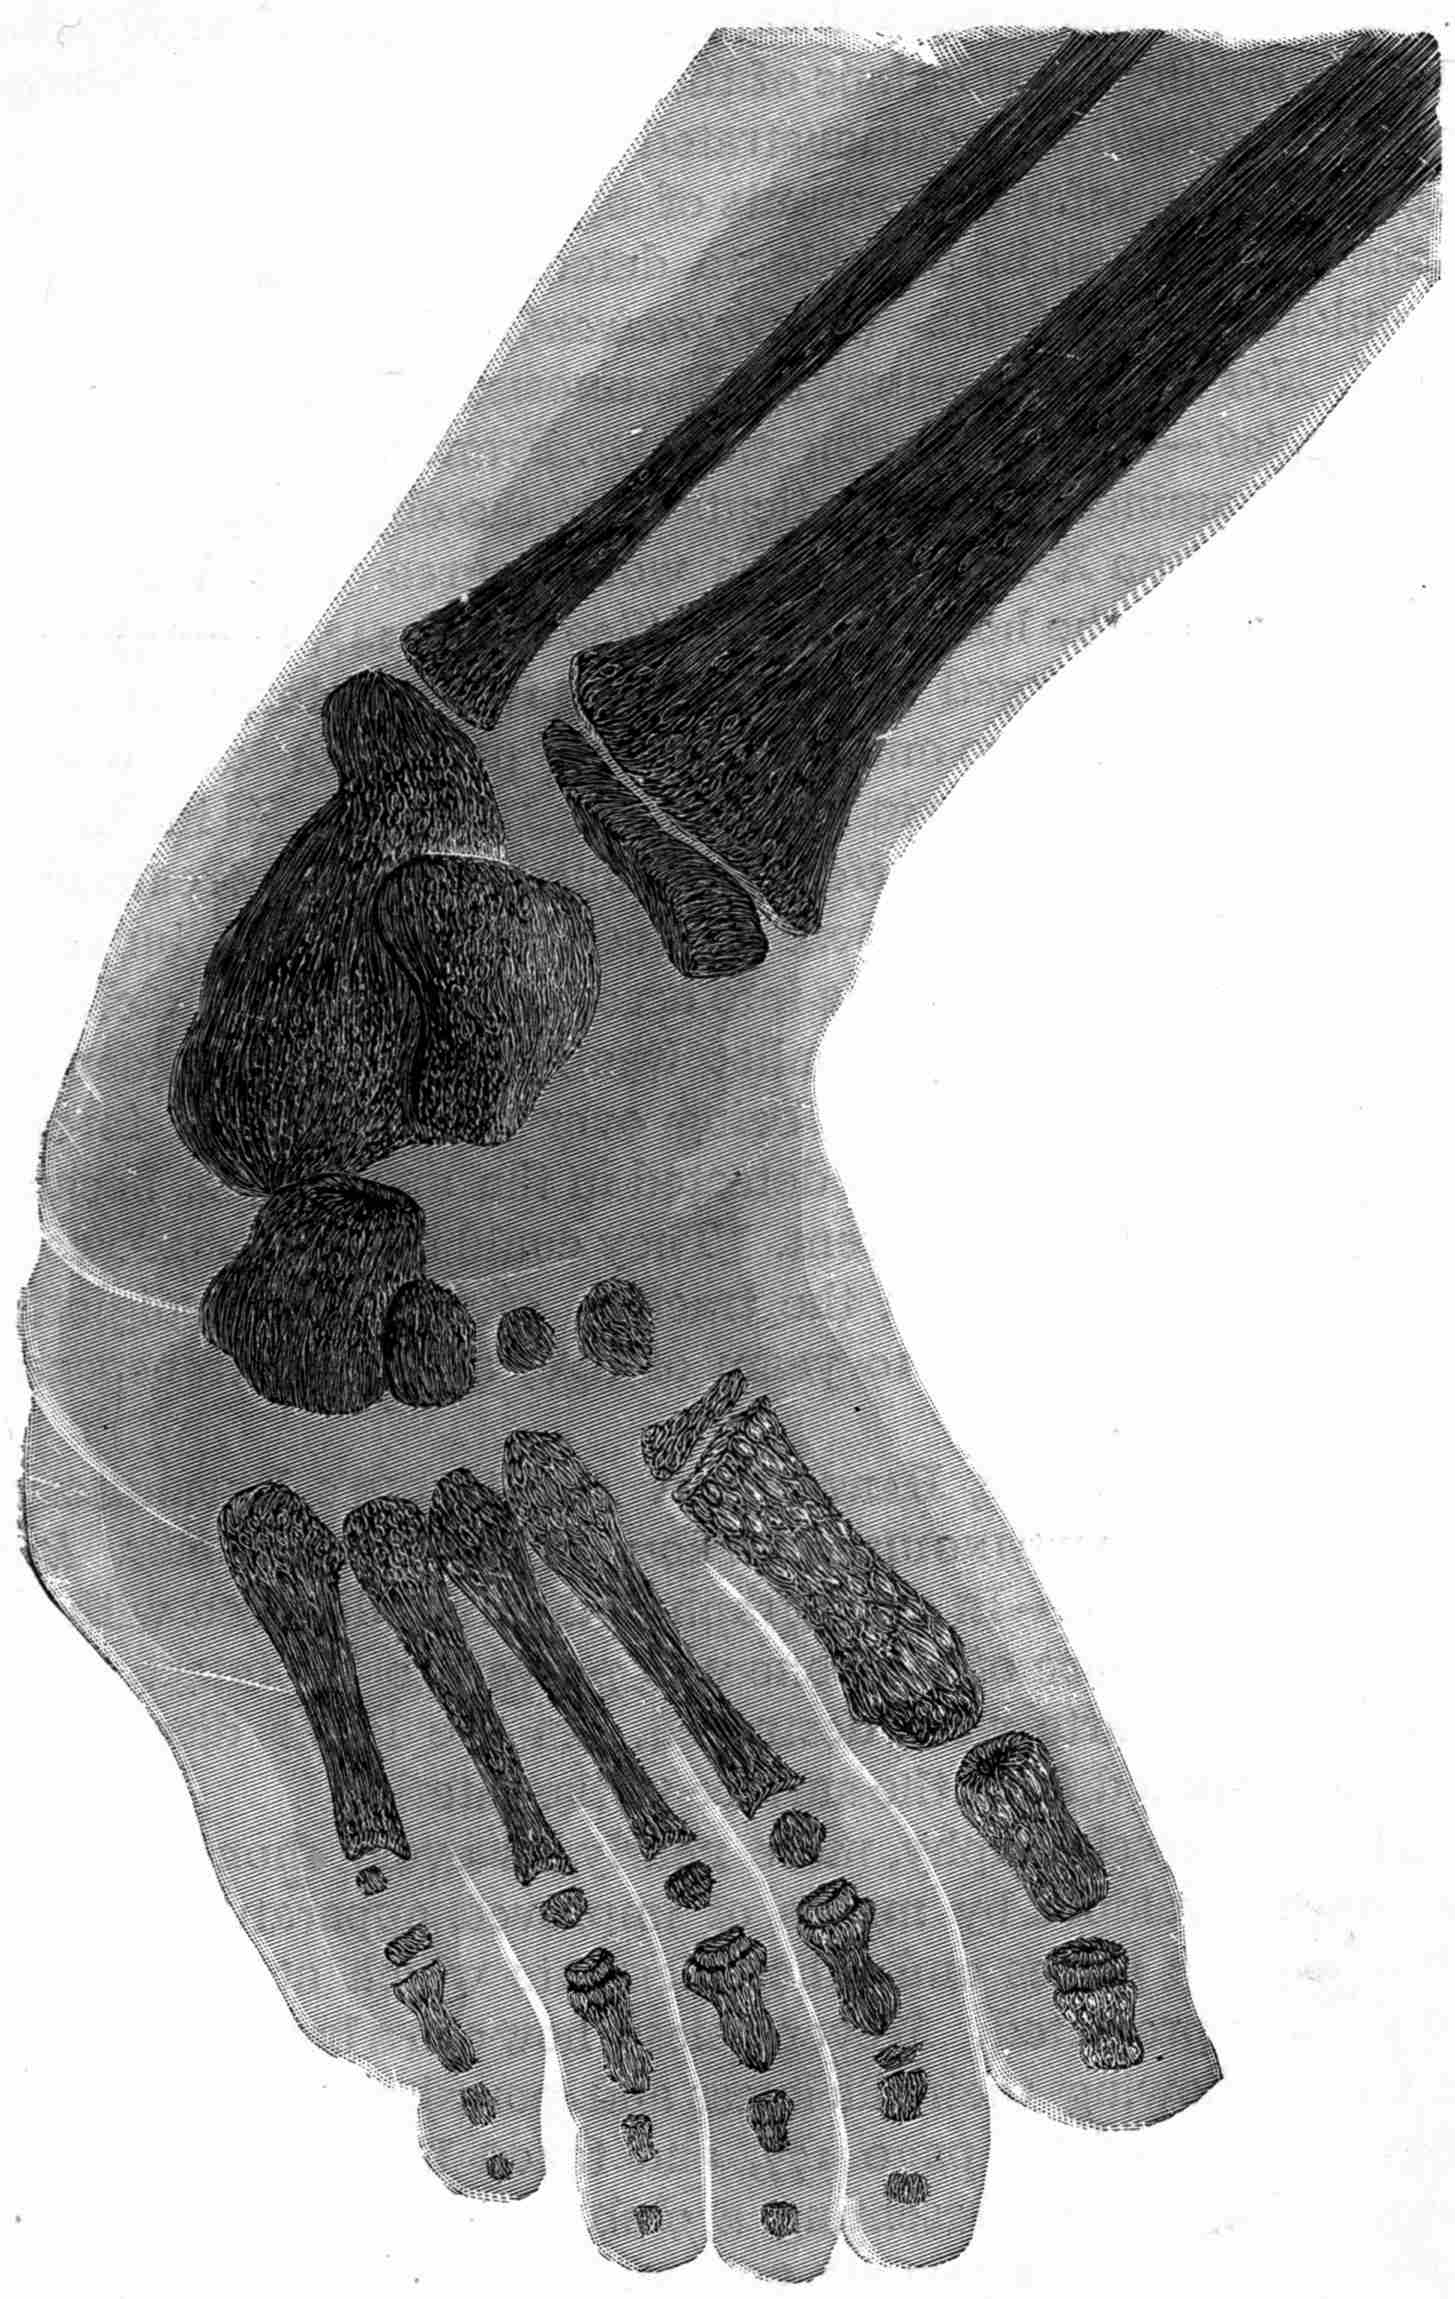

Fig. 1.—Head.

Fig. 2.—Broken Arm, Overlapping.

(Due to defective setting.)

Fig. 3.—Ribs.

Fig. 4.—Knee, Knickerbocker Buttons, Bullet in Femur.

FROM SCIAGRAPHS BY PROF. DAYTON C. MILLER. § 204.